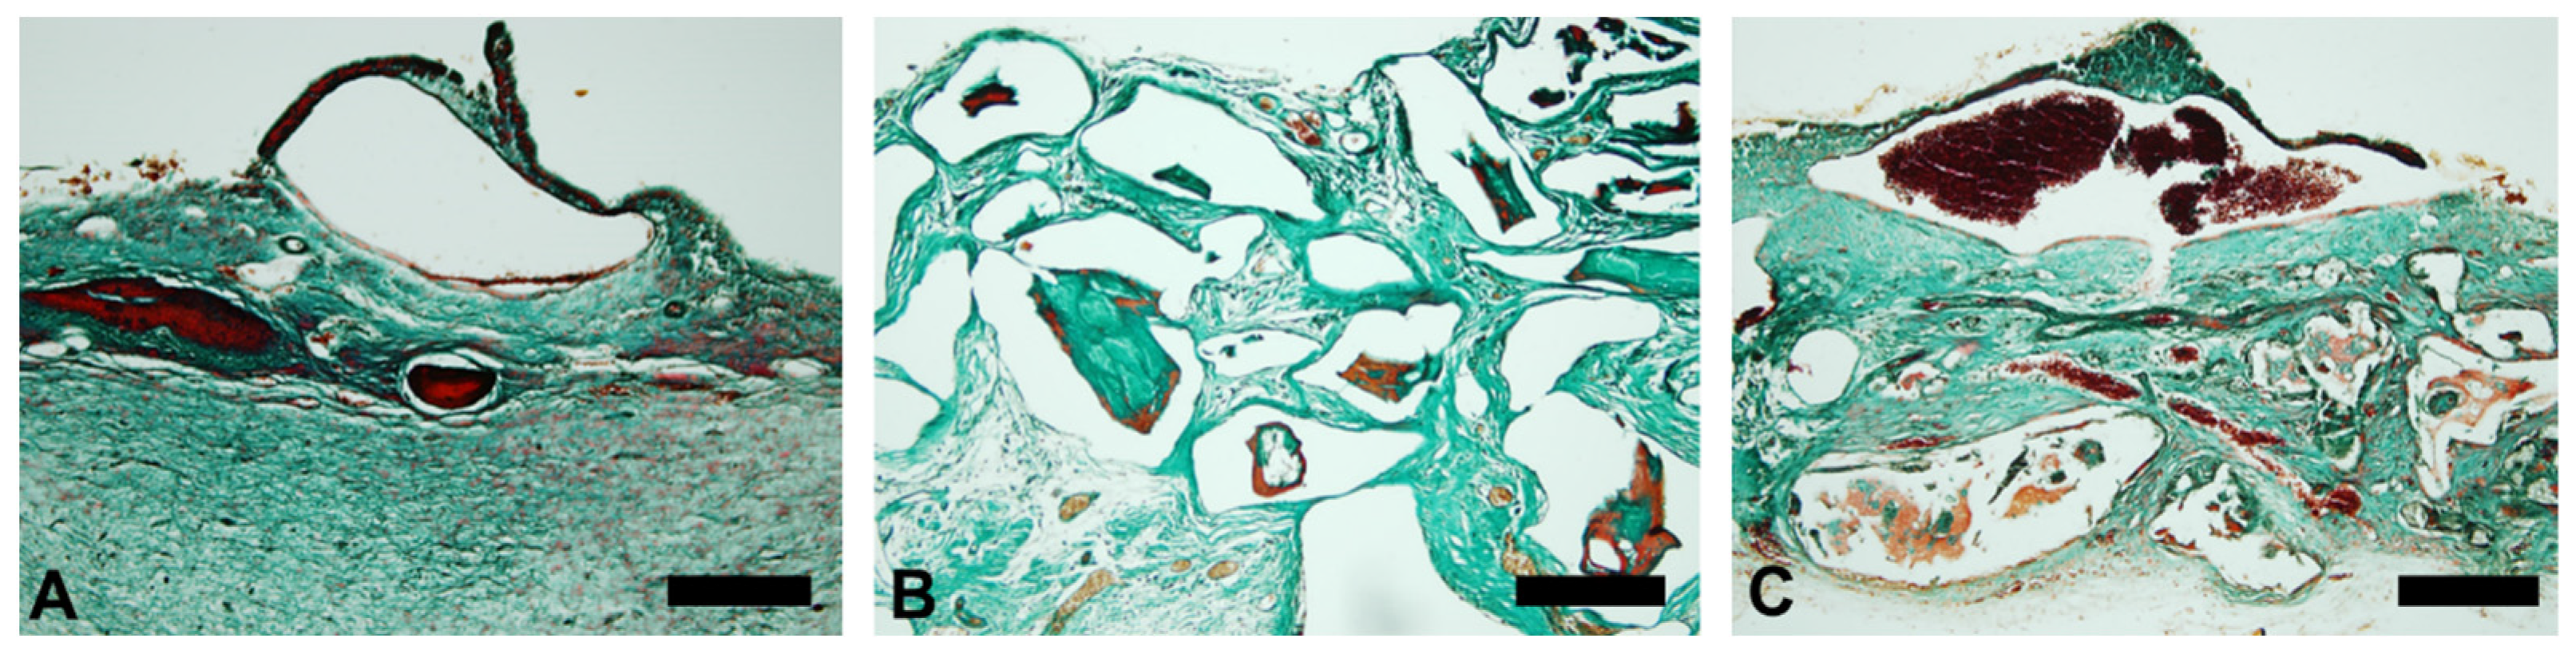

3.2. Osteopontin

3.3. Vascular Endothelial Growth Factor (VEGF)

| Mean | 0.516 | 0.3936 | 4.685 |

| Std. Deviation | 0.314 | 0.3981 | 3.405 |

| p value | 0.0001 | ||

| Exact or approximate p value? | Exact | ||

| p value summary | *** | ||

| Kruskal–Wallis Test | |||

|---|---|---|---|

| Mean | 1.447 | 5.804 | 8.279 |

| Std. Deviation | 1.024 | 3.36 | 3.823 |

| p value | 0.0072 | ||

| Exact or approximate p value? | Exact | ||

| p value summary | *** | ||

| Kruskal–Wallis Test | |||

|---|---|---|---|

| Mean | 1.778 | 4.439 | 10.71 |

| Std. Deviation | 0.7124 | 1.049 | 2.068 |

| p value | 0.0001 | ||

| Exact or approximate p value? | Exact | ||

| p value summary | *** | ||